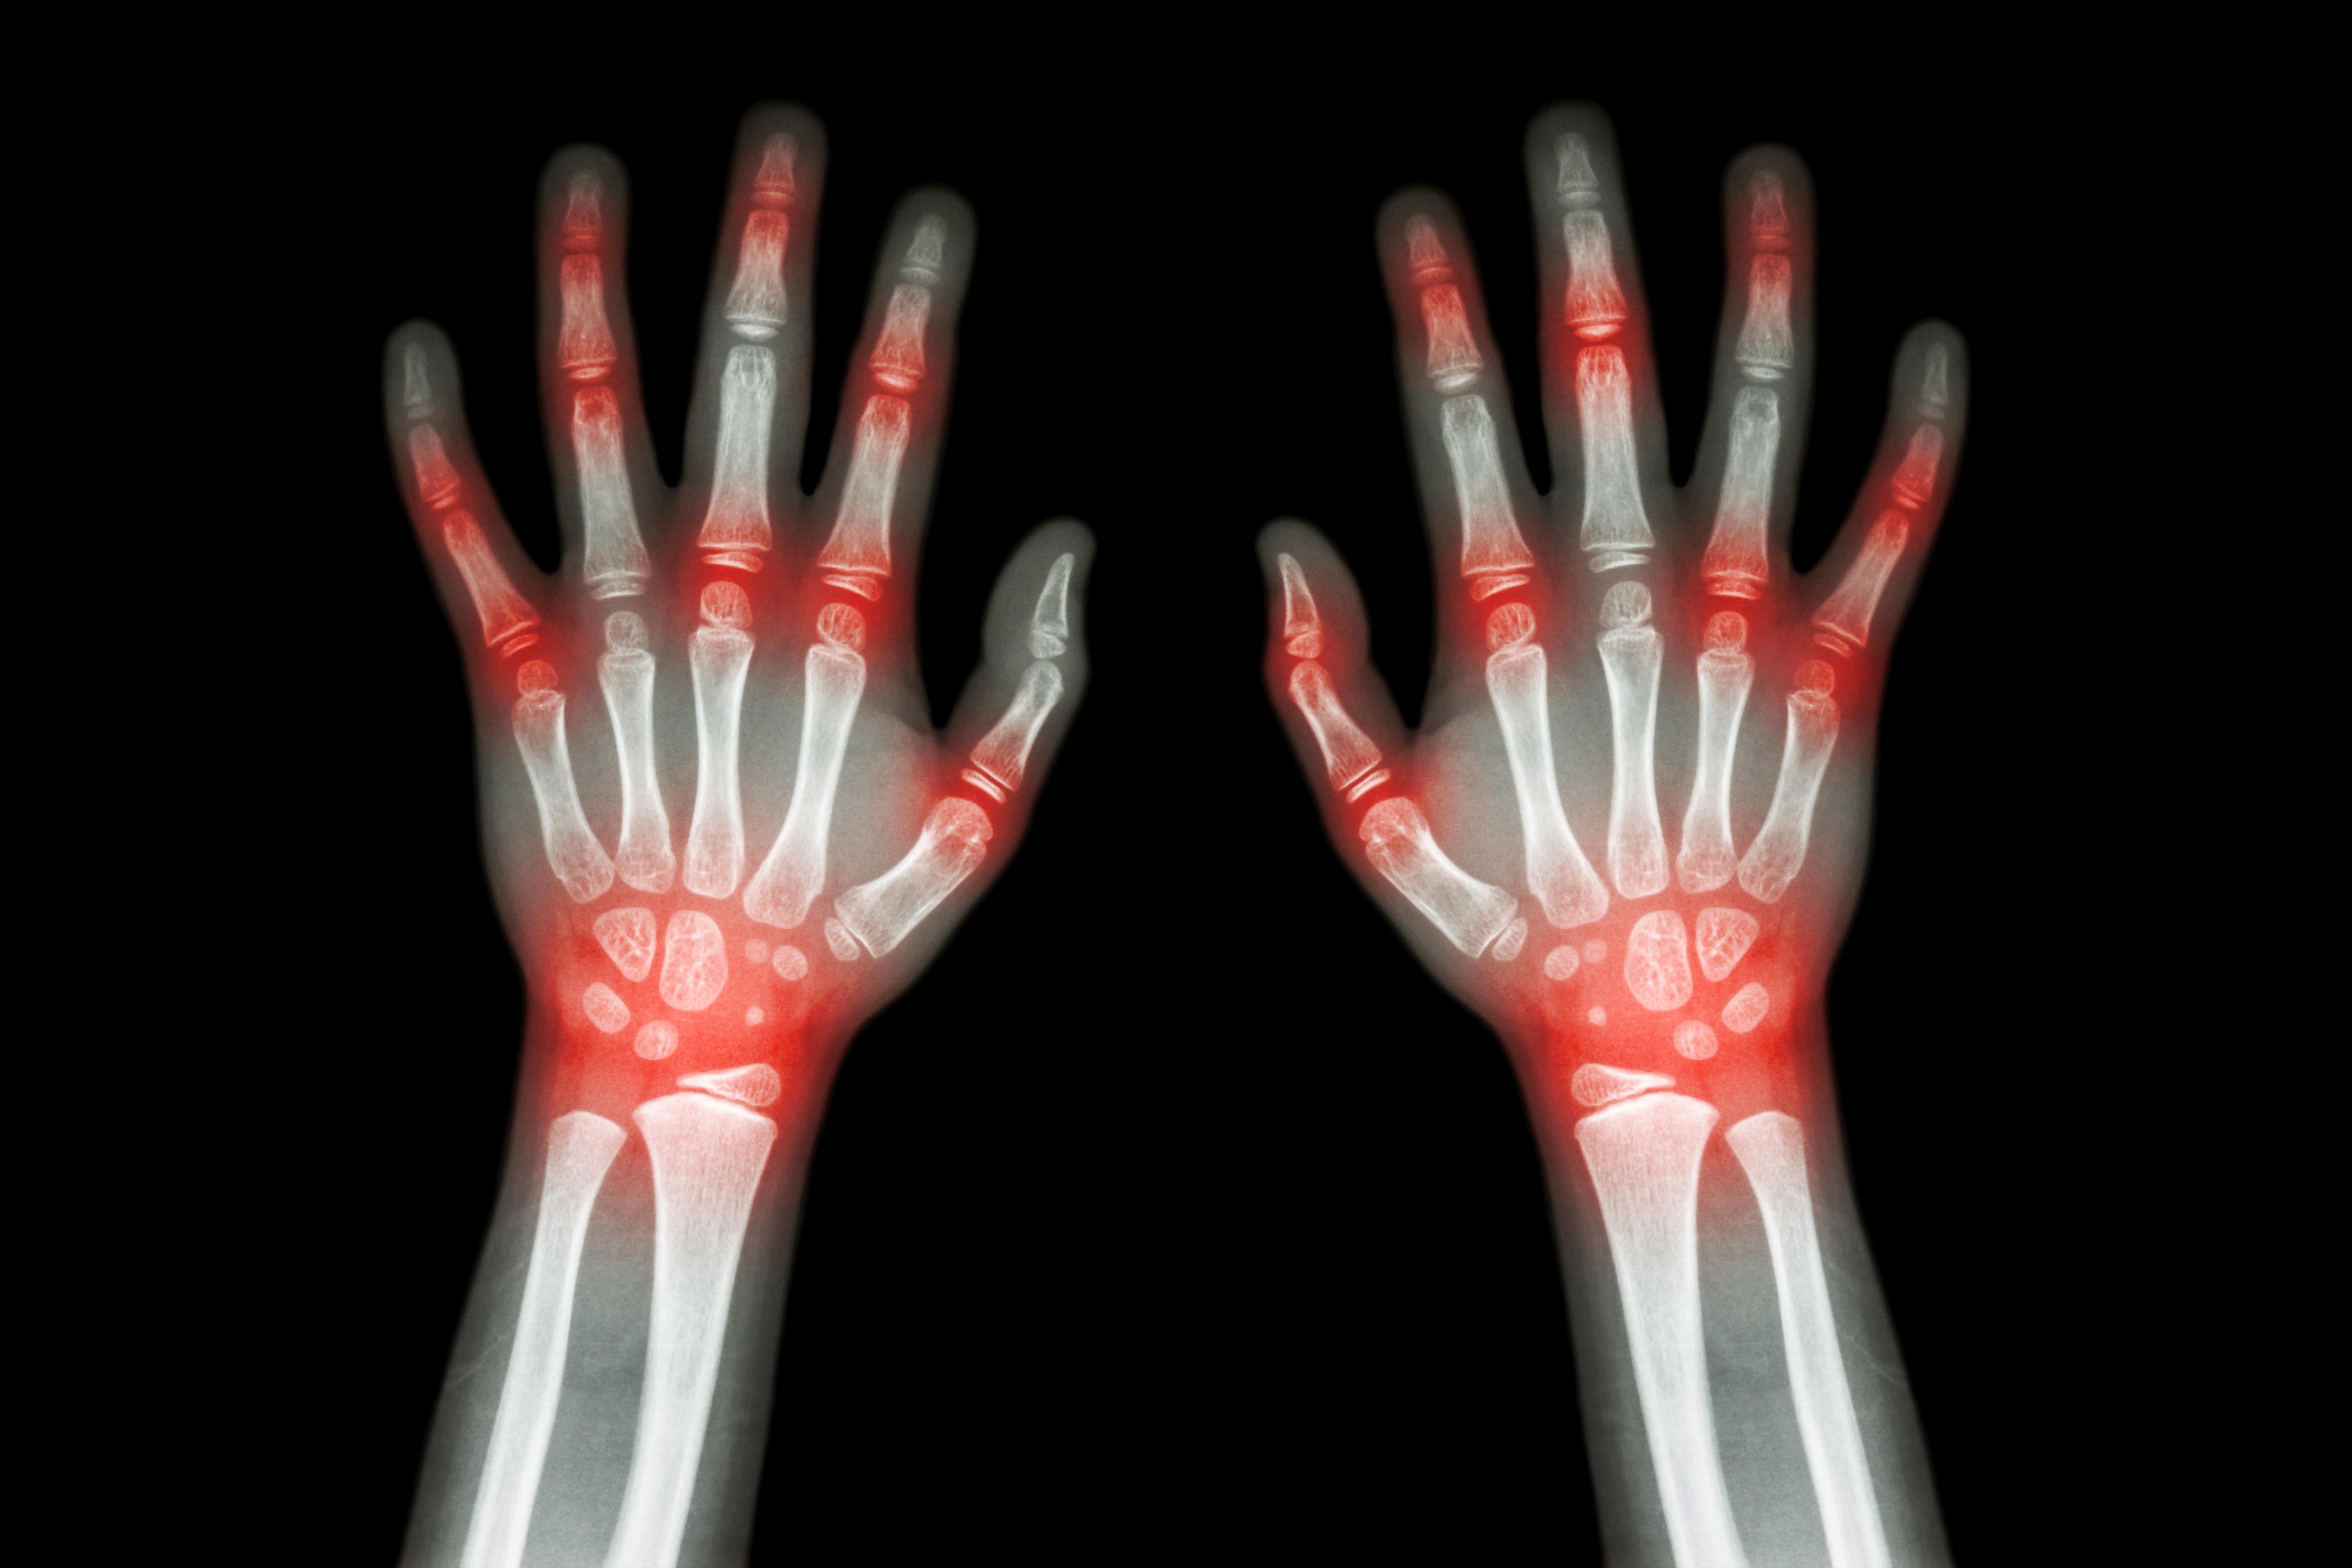

Artritis Foto: Puwadol Jaturawutthichai / Alamy / Alamy / Profimedia Artritis Foto: Puwadol Jaturawutthichai / Alamy / Alamy / Profimedia Artritis Foto: Puwadol Jaturawutthichai / Alamy / Alamy / Profimedia Ima li leka za artritis: Naučnici kažu da ova hrana mnogo pomaže kod bolova autor: N1 Zdravlje 19. jan. 2025. 15:15 0 Podeli vest: Artritis je jedno od najčešćih hroničnih zdravstvenih stanja, a za koje se vezuju brojni mitovi. Podeli vest: Oglas Ono što možda niste znali je da postoji više od 100 različitih vrsta artritisa i srodnih bolesti. Stoga ne čudi što se za ovo stanje vezuju razni mitovi i zablude. Iako je artritis često povezan sa starenjem, on može uticati na ljude svih starosnih dobi. Više od jedne trećine ljudi koji žive sa ovim stanjem kaže da to ometa njihovu sposobnost da rade i uživaju u životu. Uprkos njegovoj rasprostranjenosti, mnoga pogrešna shvatanja o artritisu i dalje postoje, što dovodi do zabune oko njegovih uzroka, lečenja i strategija upravljanja. Artritis pogađa samo starije odrasle osobe „Iako se artritis može činiti češćim kod starije populacije, on svakako nije ograničen na određenu starosnu grupu i može da utiče na ljude bilo kog uzrasta“, objasnila je dijetetičarka Sara Šlihter za „Eating Well“. Iako je tačno da je osteoartritis češći kod starijih zbog habanja zglobova, artritis ne prepoznaje starost. Stanja kao što su reumatoidni artritis, juvenilni idiopatski artritis i psorijatični artritis mogu se razviti kod mlađih odraslih, pa čak i dece, prenosi N1info.rs. Istina je da genetika, infekcije, povrede i životne navike mogu povećati rizik od razvoja bolesti, bez obzira na godine. Pucanje u zglobovima izaziva artritis Verovatno ste bili upozoreni da pucanje zglobova može dovesti do artritisa. Međutim, ovaj rasprostranjeni mit verovatno potiče od zvuka pucketanja, koji bi neki mogli da protumače kao štetan za zglobove. Iako nema opsežnog istraživanja na ovu temu, nekoliko studija nije pokazalo vezu između pucanja zglobova i razvoja artritisa. Umesto toga, veruje se da zvuk dolazi od oslobađanja mehurića gasa u sinovijalnoj tečnosti koja ublažava zglobove, a ne od trljanja kostiju jedne o drugu. Iako pucketanje zglobova može smetati onima oko vas, nije štetno za vaše zglobove i neće dovesti do artritisa. Vežbanje pogoršava artritis Za one koji žive sa artritisom, strah od pogoršanja bola ili oštećenja zglobova često znači da će biti manje fizički aktivni. Međutim, sedentarni način života može zapravo pogoršati simptome artritisa tokom vremena. „Fizička aktivnost, kretanje, svakako maksimalno do granice bola ili snage, može da omogući bolju pokretljivost i psihološki efekat da pacijent ne padne moralno (ne klone duhom), ali se ipak bori i ne predaje se bolesti, što je nažalost i dalje najčešće. Pri tome ne treba zanemariti propisanu medikamentoznu terapiju“, rekao je Nenad Horvat, predsednik Udruženja Remisija. Istraživanja ukazuje na to da vežbanje može biti korisno jer jača mišiće oko zglobova, poboljšava fleksibilnost i smanjuje upalu. Osim toga, može sprečiti razgradnju hrskavice i smanjti bolove i ukočenost zglobova. Fizička aktivnost sa malim opterećenjem zglobova poput šetnje, vožnje bicikla ili vežbanja na eliptičnim spravama mogu biti korisne. Ipak, ukoliko imate artritis, razgovarajte sa svojim lekarom ili fizioterapeutom pre upuštanja u bilo koji program vežbanja. On će vam pomoći da odredite najbolju vrstu fizičke aktivnosti za vaše lične potrebe. Sve vrste artritisa su iste Artritis se često tretira kao individualno stanje. Međutim, to je krovni izraz za mnoštvo poremećaja koji utiču na zglobove. Dva najčešća tipa su osteoartritis i reumatoidni artritis – imaju različite uzroke i mogućnosti lečenja. je najčešći tip artritisa, koji se karakteriše progresivnom razgradnjom zglobnog tkiva tokom vremena. Iako je tačan uzrok nepoznat, može oštetiti hrskavicu, tetive, ligamente, kosti i još mnogo toga. Za poređenje, reumatoidni artritis je autoimuni poremećaj u kojem imuni sistem greškom napada zglobove. Ovo može izazvati upalu i oštećenje zglobova, što može dovesti do bola, ukočenosti i otoka. Ako osetite bol u zglobovima, konsultujte svog lekara radi pravilne dijagnoze. Razumevanje uzroka i lečenja vašeg specifičnog tipa artritisa je ključ za bolje upravljanje artritisom. Ne možete ništa da uradite u vezi sa artritisom Iako je artritis hronično stanje koje se ne može izlečiti, postoje mnoge strategije koje će vam pomoći da upravljate simptomima i poboljšate kvalitet života, uključujući promene u ishrani. „Dijeta može uticati na simptome artritisa, a fokusiranje na hranu protiv upale, kao što su morski plodovi, voće i povrće, pa čak i određeni suplementi, može ublažiti simptome“, dodao je Šlihter. Iako ne postoji jedinstvena dijeta osmišljena da ublaži simptome artritisa, mediteranska ishrana mogla bi da bude najprikladnija. To je zato što je puna antiinflamatorne hrane poput masne ribe, voća, povrća, orašastih plodova i semenki. Istraživanja ukazuje na to da bi ovaj tip ishrane mogao da bude posebno koristan za reumatoidni artritis. Strategije za upravljanje artritisom Ako živite sa artritisom, evo nekih strategija zasnovanih na dokazima koje mogu smanjiti bol: – Uključite vežbe sa malim opterećenjem kao što su plivanje, biciklizam ili hodanje u svoju svakodnevnu rutinu da biste poboljšali zdravlje i pokretljivost zglobova. – Držite se antiinflamatorne ishrane koja uključuje hranu poput voća, povrća, orašastih plodova, semenki, integralnih žitarica, mahunarki i masne ribe. – Prekomerna telesna težina vrši pritisak na vaše zglobove, koji se vremenom mogu dodatno istrošiti. Kontrola težine može pomoći da se ublaži ovaj pritisak i bol koji dolazi sa njim. – Život sa hroničnim zdravstvenim stanjem, kao što je artritis, može biti stresan. Veza je toliko jaka da su studije otkrile da ljudi sa reumatoidnim artritisom često doživljavaju pojačane simptome kada su pod stresom. – Uključivanje naučnih tehnika za upravljanje stresom, kao što su svesnost, meditacija i terapija, može pomoći da se smiri vaš um, a možda i simptomi. Najraniji simptomi artritisa koje većina ljudi ignoriše pre nego što bude kasno Zdravlje 0 Da li pucketanje zglobova izaziva artritis? Zdravlje 0 artritis mediteranska ishrana Pratite nas na društvenim mrežama: Koje je tvoje mišljenje o ovoj temi? Učestvuj u diskusiji ili pročitaj komentare Budite prvi koji će ostaviti komentar Pošalji komentar Pročitaj komentare (0)